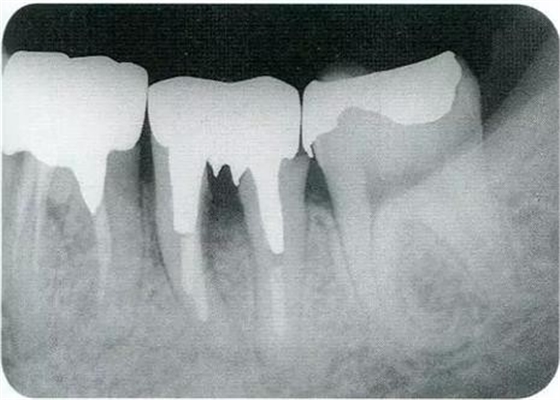

▼圖16-3

圖16-3對(duì)右上6.7顎側(cè)根的頰側(cè)牙槽中間骨脊缺失進(jìn)行處理,對(duì)應(yīng)高度來(lái)對(duì)右上5遠(yuǎn)中牙槽骨進(jìn)行少量切除。之后,對(duì)應(yīng)右上5遠(yuǎn)中牙槽骨的高度對(duì)近中以及右上4的牙槽骨進(jìn)行治療處理。牙槽骨的整體形態(tài)盡可能平坦,沒有極端的段差留下。之后,通過(guò)apically positioned flap進(jìn)行縫合固定。結(jié)果就能提高術(shù)后清潔性,得到良好的牙周環(huán)境。